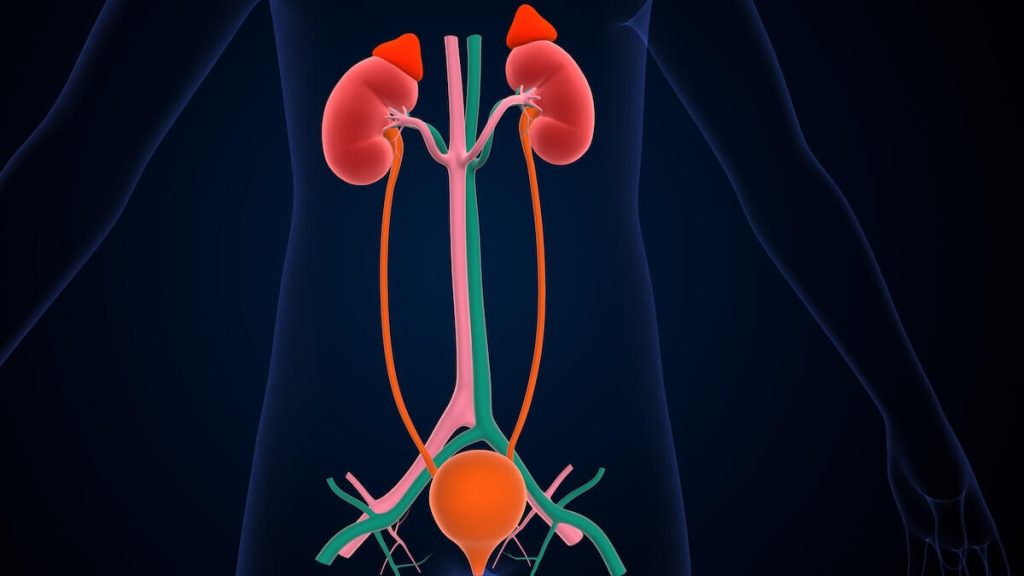

Adrenal gland disorders refer to conditions where the adrenal glands, which are located on top of the kidneys, do not function as they should. The adrenal glands produce important hormones such as cortisol, aldosterone, and adrenaline. Disorders in the adrenal glands can lead to an imbalance in these hormones, causing a variety of symptoms and health issues.